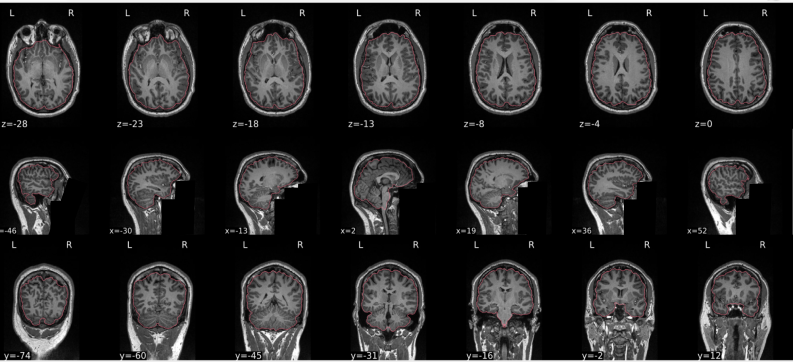

dT1w spatial normalisation

This QC step shows the registration of the T1 image to MNI space.

The registered T1 image is shown in the background with a brain atlas in MNI space as an overlay.

Example of a bad subject

- In case of poor registration, you should see a misalignment between the MNI template and the T1 (e.g., brain shifted down).

Summary

| good | bad |

|---|---|

| Structures of the MNI template and the registered T1 are well aligned | Structures of the MNI template and the registered T1 aren’t well aligned, e.g. brain is shifted downwards |